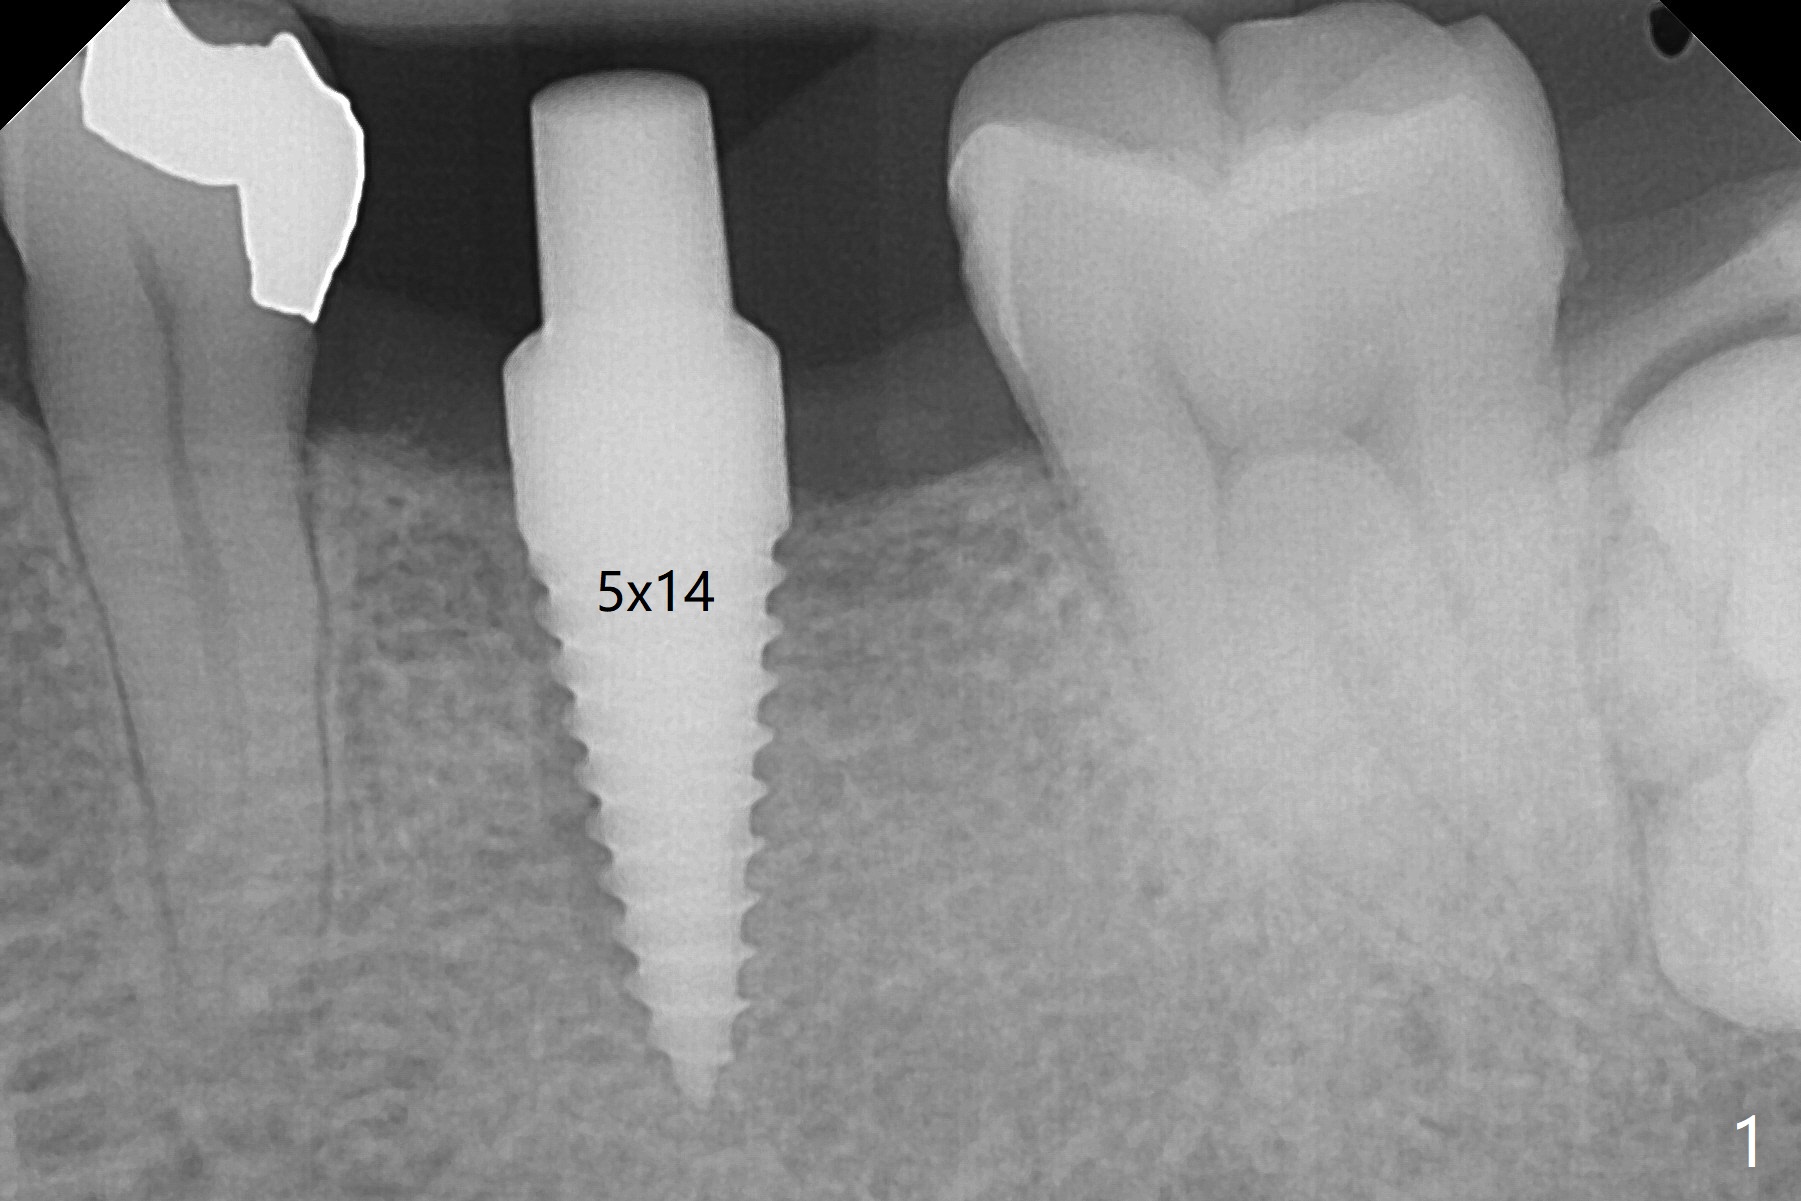

适当更改导板(为两段式接近圆柱状植体设计)钻洞顺序(根尖钻头小,而一段式植体根尖特别尖),5x14毫米一段式软组织水平植体植入,扭力大约35Ncm(图一),略微种深(图二:长箭头)后,磨短基台(与图一对比;左上6伸长),颊侧,远中,舌侧边缘降低(图二,三:<;增加基台高度,提高牙冠固位),制作临时牙冠(图四:P),主要目的将近中牙龈推向近中(图三:空箭头),暴露近中基台边缘,以后好取模。总之,一段式植体需要考虑临时修复。术后两个月临时牙冠和周围牙龈正常(图五)。术后4.5月轻度骨质吸收(图六),临床上看不出来螺纹将要暴露,取模。病人抱怨用临时牙冠咀嚼疼痛,不咬后没有不舒服,其实临时牙冠咬合面穿孔,牙龈正常,永久粘固剂没有外溢(图七)。术后4.5-6个月植体周围骨质吸收(图六,七)。牙槽嵴处钻洞应与植体直径一样才能减少骨质吸收。